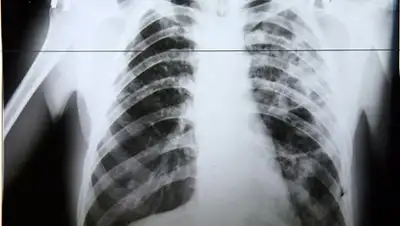

Туберкулез коварен тем, что развивается медленно, имеет  хронически текущее течение

Туберкулез коварен тем, что развивается медленно, имеет  хронически текущее течение. Как отметила старший научный сотрудник отдела хирургического лечения внелегочного туберкулеза  Национального центра проблем туберкулеза (НЦПТ)  Ляйля Аманжолова,  туберкулез  внелегочной  локализации может протекать под маской других  болезней, таких как остеохондроз, радикулит, невриты  и даже онкологические заболевания, что затрудняет своевременное  установление  диагноза.

Пациент Б. Национального Центра проблем туберкулеза, заболел ТБ  в местах лишения свободы. Пройдя начальный  курс лечения и почувствовав улучшение самочувствия, пациент своевольно прервал  лечение и через определенное время  вновь попал в тубдиспансер уже с осложненным клиническим диагнозом: фиброзно-кавернозный туберкулез легких,  категория 4, множественная лекарственная устойчивость. И теперь уже 100-процентная гарантия на полное выздоровление  будет зависеть не столько от участия медицинских работников, сколько от общего состояния организма и психологического настроя пациента на завершение полного контролируемого лечения. При общении со мной пациент признался, что очень сожалеет о своем необдуманном поступке в прошлом и теперь позитивно настроен на завершение полного курса лечения.

Туберкулез  излечим, но  все  еще представляет  серьезную  угрозу  для человека,  если  его недооценивать.  Не вылеченный туберкулез легких, при его прогрессировании, может привести  к генерализации процесса заболевания, к разрушению органов с массивным кровохарканьем  и к медленной мучительной смерти, сопровождающейся сердечно-легочной недостаточностью, то есть нехваткой воздуха  и неспособностью дышать.